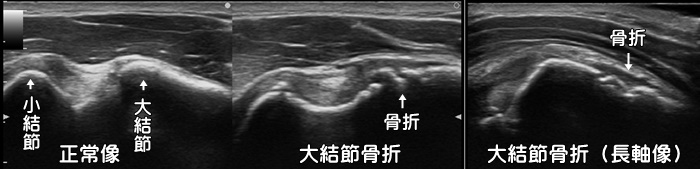

上腕骨大結節骨折

転倒などで肩部を強打すると上腕骨の凸部である大結節を骨折します。上記症例はレントゲンでは異常が確認できず、MRIにて確定診断されました。エコーでは小さな骨片や炎症反応が強く見られます。